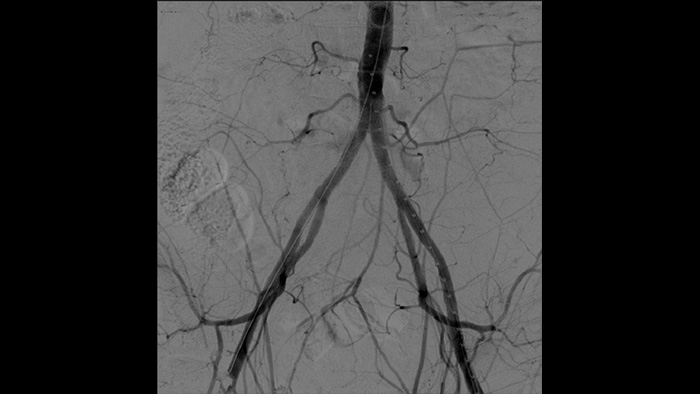

Com o arco cirúrgico portátil Zenition da Philips, o Dr. Vila está obtendo imagens de qualidade excepcional que lhe permitem realizar a maioria dos procedimentos vasculares com uma configuração de baixa dose.

Com o Zenition, nossa qualidade de imagem de ASD melhorou muito. Não vemos mais uma imagem granulada, somente uma imagem muito clara."

Dr. R. Vila, MD

Hospital Universitário de Bellvitge, Barcelona, Espanha

A angiografia por subtração digital (ASD) é usada em procedimentos vasculares intervencionistas para visualizar os vasos sanguíneos com clareza, removendo estruturas que podem obscurecer a visibilidade dos vasos. A fluoroscopia do roteiro sobrepõe uma imagem com contraste subtraída adquirida anteriormente à fluoroscopia ao vivo, permitindo que você monitore um dispositivo sem reinjetar contraste.